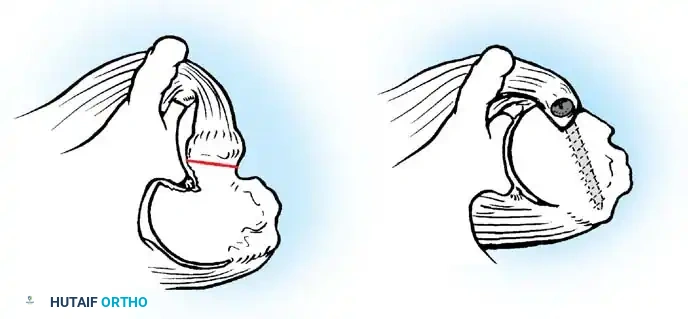

The Bankart Lesion and Capsular Failure

In 1906, Perthes first described the detachment of the anteroinferior labrum. In 1938, Bankart popularized the concept, describing the traumatic detachment of the fibrocartilaginous labrum and anterior capsule from the glenoid rim—now universally known as the Bankart lesion. Rowe et al. identified Bankart lesions in 85% of traumatic recurrent dislocations.

However, capsular laxity is equally detrimental. Rowe found excessive laxity in 28% of traumatic dislocations and 86% of failed surgical stabilization procedures. This laxity can stem from congenital collagen deficiencies (e.g., Ehlers-Danlos, Marfan syndrome) or plastic deformation from repetitive microtrauma.

Baker et al. arthroscopically evaluated acute dislocations, finding that 38% involved intrasubstance ligamentous failures, while 62% were avulsions from the glenoid. Bigliani et al. biomechanically tested the IGHL complex, revealing that failure occurs at the glenoid insertion (40%), midsubstance (35%), or the humeral insertion (25%). Humeral avulsion of the glenohumeral ligament (HAGL lesion), noted by Wolf et al. in 9% of acute dislocations, is a critical pathology that must not be missed, as standard Bankart repairs will fail to address it.

Capsulotomy and Joint Inspection

A vertical or T-shaped capsulotomy is performed based on the degree of capsular laxity and the planned shift.

- For a standard Bankart repair with an inferior capsular shift, a vertical incision is made 1 cm medial to the humeral articular margin. A horizontal limb can be added to create superior and inferior capsular flaps.

- Tagging sutures are placed in the capsular flaps for traction.

- A Fukuda retractor is placed within the joint to retract the humeral head laterally and posteriorly, exposing the anterior glenoid rim and labrum.